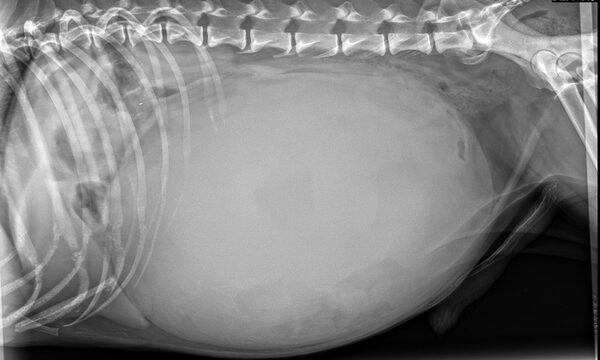

Sammy, ein fast 13 jähriger Mischlings-Rüde, wurde uns wegen seines stark aufgetriebenen Bauchs vorgestellt.

Eine Röntgenuntersuchung zeigte eine Masse, die den gesamten Bauchraum ausfüllte und alle anderen Organe stark verdrängte. Sie führte bereits zu einer erschwerten Atmung.

Trotz Sammys fortgeschrittenem Alter entschied sich sein Herrchen mutig zu einer Operation.

In der Operation zeigte sich, dass es sich um eine riesige, flüssigkeitsgefüllte Masse des Gekröses handelte. Wir entfernten sie erfolgreich. Vor der Operation wog Sammy 20 kg, danach nur noch 16,2 kg. Die Masse wog also 3,8 kg. Fast ein Viertel seines ursprünglichen Gewichts.

Direkt nach der Operation schien es Sammy schon deutlich besser zu gehen.

Die histopathologische Untersuchung ergab eine gutartige Veränderung.